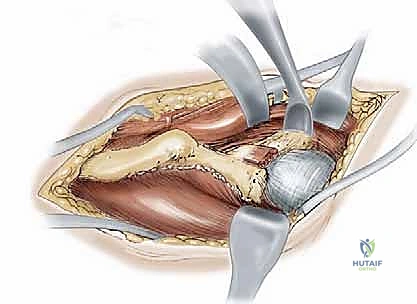

1. النهج الجراحي (The Surgical Approach)

يستخدم الدكتور هطيف شقاً جراحياً تجميلياً يُعرف بـ (Bikini Incision) أو نهج (Smith-Petersen) المعدل. يسمح هذا النهج بالوصول إلى جميع أجزاء الحوض الأمامية والداخلية دون قطع العضلات الرئيسية، بل يتم فصل العضلات وإبعادها بلطف (Muscle-sparing approach)، مما يسرع التعافي بشكل كبير.

2. سلسلة قطع العظام (The 5 Osteotomies)

يكمن سر نجاح جراحة PAO في إجراء خمسة قطوع عظمية منفصلة حول الحُق، لتحريره بالكامل عن باقي الحوض، مع ترك العمود الخلفي سليماً كدعامة أساسية.

القطع الأول: القطع الإسكي غير المكتمل (Incomplete Ischial Osteotomy)

باستخدام إزميل خاص ذو زاوية (Angled Osteotome)، يتم إجراء قطع في عظم الإسك أسفل الحُق مباشرة (في الأخدود تحت الحُقي). يتم هذا القطع بتوجيه الأشعة السينية (Fluoroscopy) لضمان عدم اختراق المفصل. يحرص الدكتور هطيف على إبعاد العصب الوركي والأوعية السدادية بأمان تام.